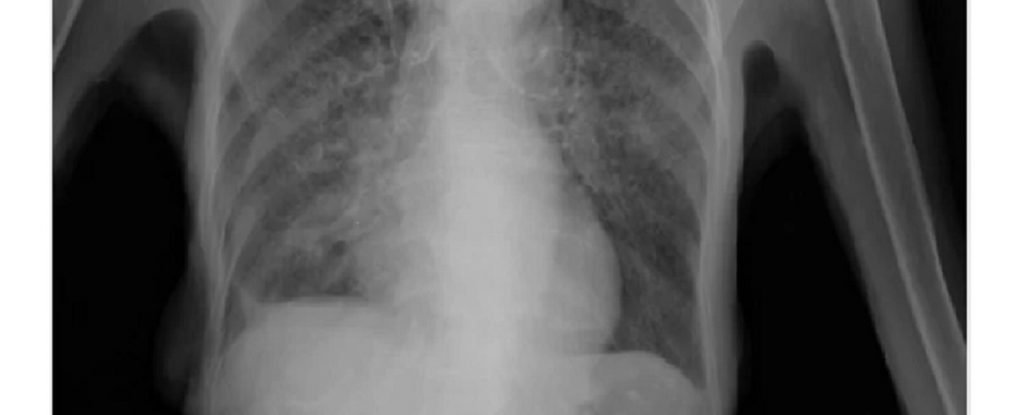

रायगड जिल्ह्यातील दहा गावांमध्ये “टीबीमुक्त पंचायत” अभियानाची सुरूवात करण्यात येत असल्याचे सांगत आयुक्त म्हणाले, पंतप्रधान नरेंद्र मोदी यांनी सन २०२५ सालापर्यंत “टीबी मुक्त भारत” करण्याचा निर्धार व्यक्त केला आहे. पंतप्रधानांच्या या महत्त्वकांक्षी योजनेतंर्गत देशभरातील १००० पंचायतींना टीबी मुक्त करण्यात येणार आहे. महाराष्ट्रातील “टीबी मुक्त पंचायत” अभियानाची सुरवात रायगड जिल्ह्यातून करण्यात येत आहे. जे एस डब्ल्यू फाउंडेशनच्या सहकार्याने रायगड जिल्ह्यातील दहा गावामधील सुमारे १० हजार नागरिकांची तपासणी करून टीबी रुग्णाचा शोध, निदान, उपचार व निर्मुलन करण्यात येणार आहे. रायगड जिल्ह्यातील अभियानाच्या यशानंतर राज्यभर “टीबी मुक्त पंचायत” अभियान राबवण्यात येणार आहे. या अभियानाला “द युनियन साऊथ इस्ट आशिया (USEA) यांचे तांत्रिक सहकार्य लाभणार असून, जे एस डब्ल्यू फाउंडेशन सी एस आर मधून आर्थिक मदत देणार आहे. या बैठकीत माय लॅबचे हँडी एक्स-रे मशीन तसेच, खोकल्याच्या आवाजावरून टीबी निदान करणाऱ्या ॲपचे प्रात्यक्षिक सादर करण्यात आले.